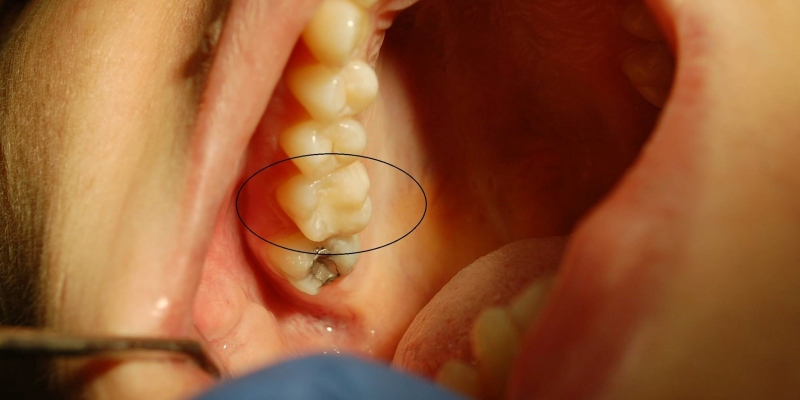

- Fotokompozitné výplne.

- Výplne zhotovené sklenenými vláknami alebo sklenenými čapmi pri endodoticky ošetrených zuboch.

- Fazety a nepriame výplne.